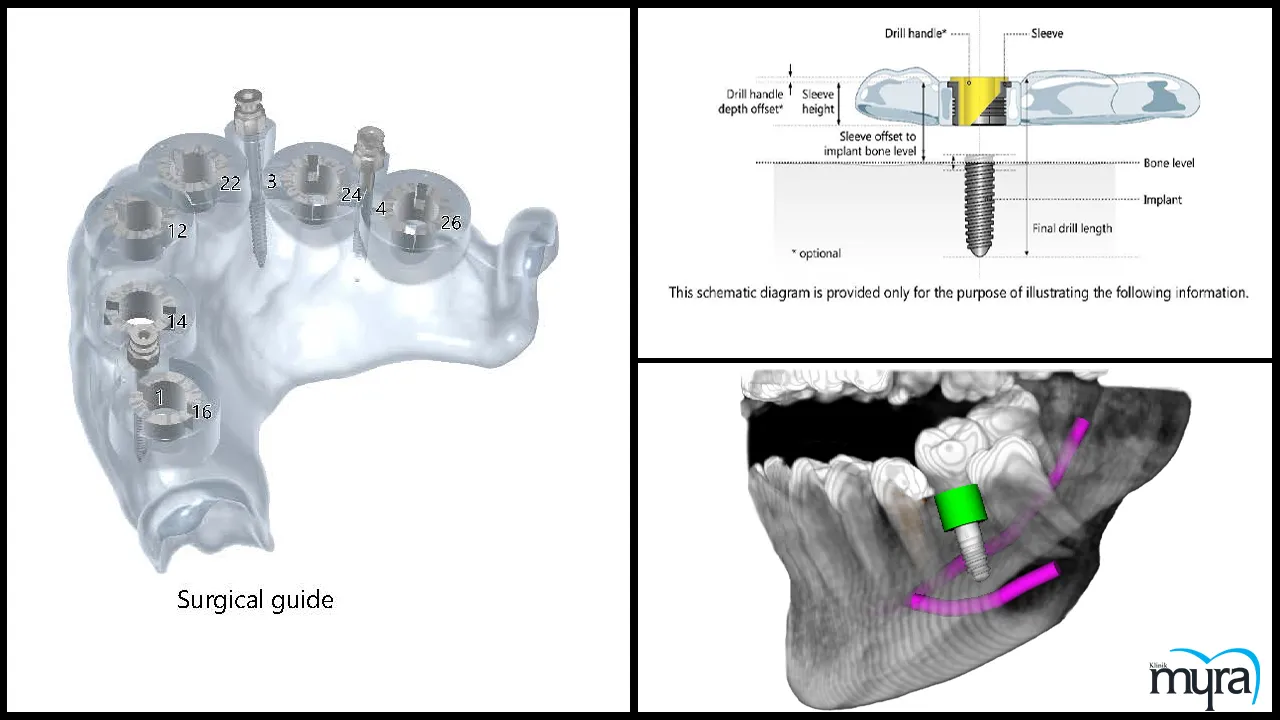

Advances In Dental Implantology